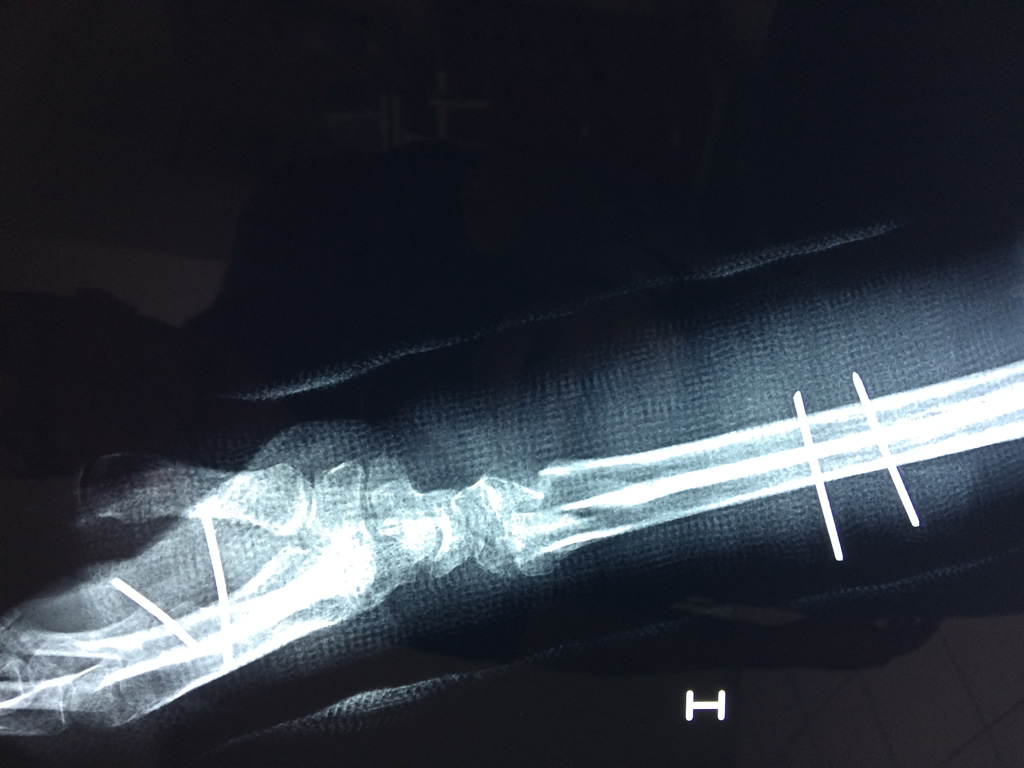

Cirugías de Calcaneo - Cirugías de Muñecas y Manos

Los procedimientos más comunes en cirugía de la mano son aquellos destinados a reparar traumatismos, incluyendo lesiones de tendones, nervios, vasos sanguíneos, y articulaciones; huesos fracturados; y quemaduras, cortes, y otros daños de la piel.